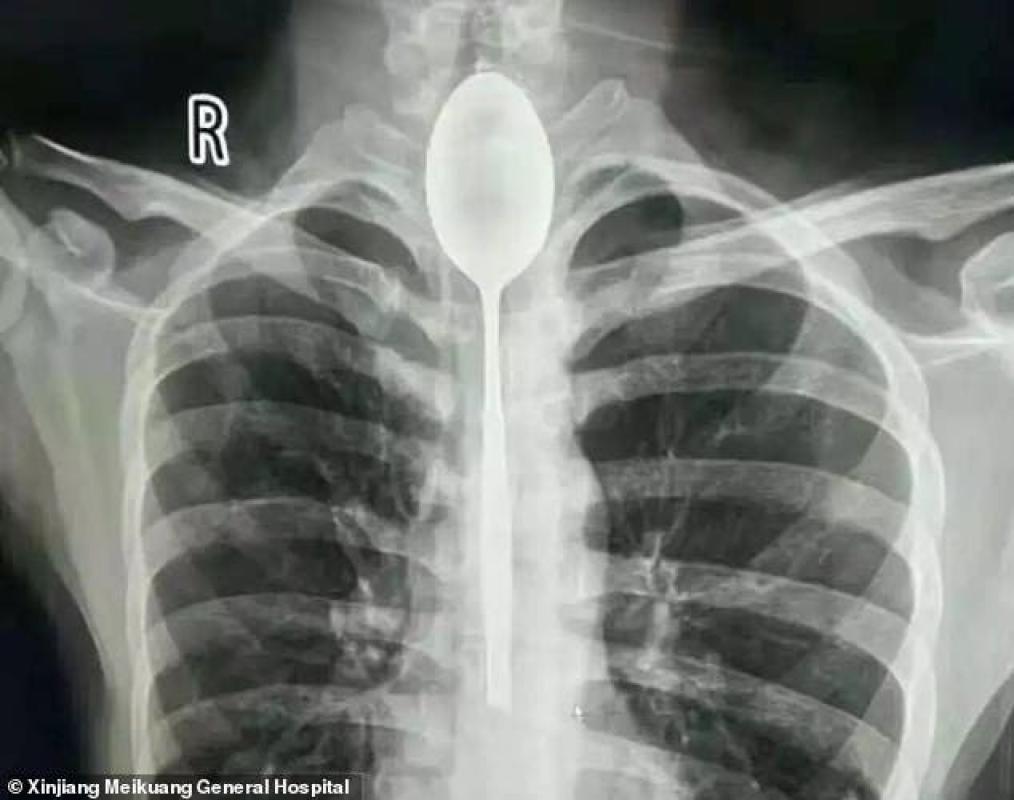

El hombre de 26 años fue sometido a una radiografía, la cual arrojó que tenía una cuchara de acero inoxidable de metal alojada en su esófago.

Tras esto, se le realizó una endoscopía y se logró extraer el utensilio de 20 centímetros de largo que estaba dentro de su cuerpo hace un año.